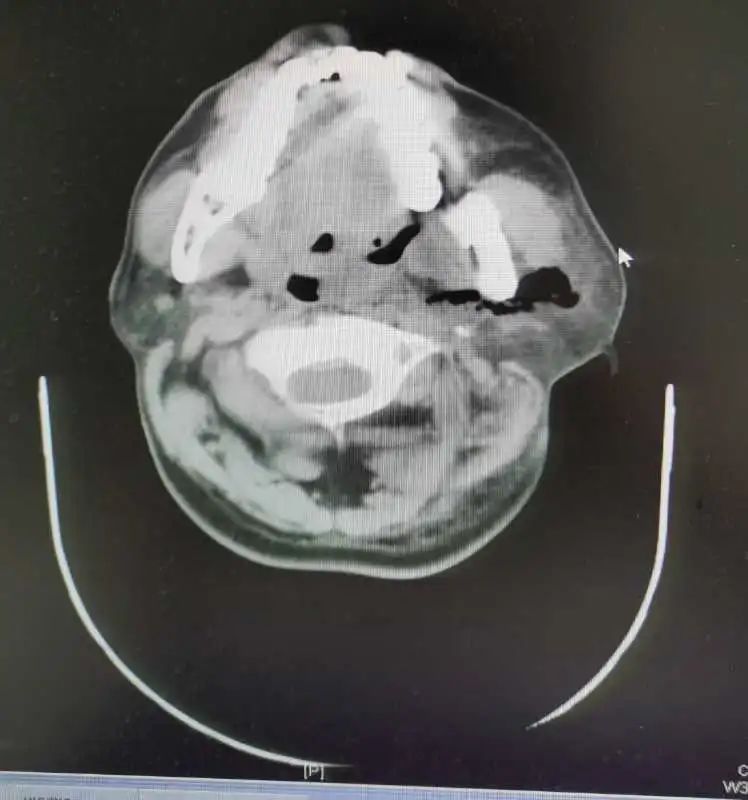

经过进一步检查显示,肖先生左侧扁桃体、左侧口咽旁、颌下、颈部、耳前、胸前壁软组织感染、脓肿形成,呈多间隙脓肿,散在大量积气,纵膈、肺部感染,脓肿尚未形成。耳鼻咽喉科医生朱先柏决定联合口腔科医师急诊下行双侧颌下、颈胸部脓肿切开探查引流术+气管切开术。

在手术后次日,肖先生口咽部、颌下区、颈胸部疼痛进一步好转,换药时引流管可冲出少量脓液。但术后第三日,患者自觉右侧颈部疼痛再次加剧,复查头颈面胸部CT回示:左侧脓肿及积气大部分吸收,肺部、纵膈感染已控制,但右侧颈部再次出现脓肿,且向深面进展。耳鼻咽喉科邓安春主任和朱先柏医师查看患者影像学检查后判断,应及时再次手术,以制止脓肿向颈动脉鞘及纵膈发展,于是当日再次急诊下行了右侧颈部脓肿切开探查引流术。